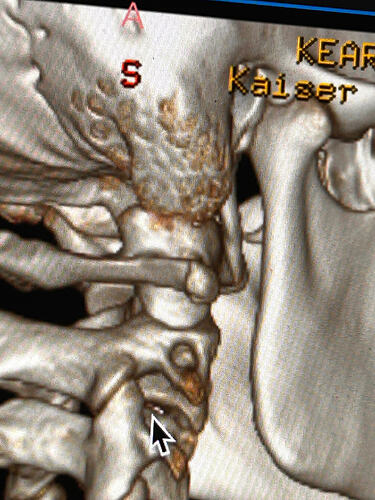

In this image of your left styloid, it appears from the angle of the picture that your left styloid is extremely close to the left transverse process of C1 (green circled area). If that’s truly the case, your left IJV is likely being squashed between the two & that means your vagus nerve is most likely being squashed at that point, too. Some of your symptoms could be vagal related. Also due to the angle of the image, it appears the greater horn of your hyoid could be very close to your spine which can cause internal/external carotid artery compression but can also cause symptoms that point to hyoid bone syndrome as you’ve suggested. Unfortunately, it doesn’t appear the CT scan was done w/ contrast as none of your veins or arteries appear in the images you posted & contrast is necessary to see those.

I’ll just add in as well that in your first image, the hyoid bone processes look pretty thick, more than you’d expect, so could well be part of your issues, but I do agree with @Isaiah_40_31 that your left styloid is very close to the C1 process, the right side looks a little longer than average… Also looking at the 1st & last images (I’m sorry, | can’t label them for you), there’s calcification below your hyoid which I’m presuming is the thyroid cartilage, it lookd pretty chunky compared to most people’s, so this could possibly be causing some issues too?

This one shows your right hyoid greater horn from behind.

I totally missed that I could see your whole hyoid bone from the front in this image. Jules is right, your greater horns are very thick from top to bottom. You can also see that your left greater horn is pretty straight, but the right one has an upward curve to it. I’m not sure what the calcification is below your hyoid but it’s most likely thyroid since the thyroid sits just below the hyoid in the neck.

In this image, you can see the differences in the shapes of your hyoid’s greater horns. The right one is more curved but the left one is thicker in width medial to lateral. In this image from the front it looks like both greater horns may be contacting your cervical spine in certain head positions, but again, that may an illusion created by the angle of the image.

In the final two images you sent, the right greater horn is very close to your cervical spine so there’s a good chance it’s causing you some problems as well as possible carotid artery irritation or compression in different head positions. The image of the left one doesn’t show as much of the greater horn so I can’t tell how close to the spine it is. Can you back the left image out a bit so it looks more like the right one?